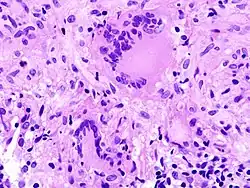

Kriterien der Malignität

- Zytologisch: Polymorphie, basophiles Cytoplasma, erhöhte Kern/Plasmarelation

- Nukleär: Polymorphie, Polychromasie, Hyperchromasie, Aneuploidie, (vergrößerte) Nukleolen, vermehrt Mitosen, atypische Mitosen, erhöhter Proliferationsindex (Ki-67 = MIB-1).

- Polymorphie - Zeichen der Malignität